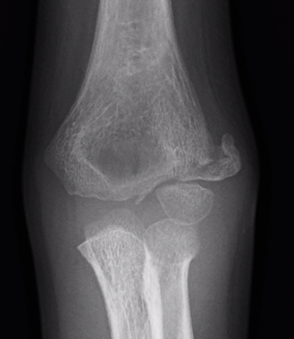

Injured left elbow v injury right elbow

Internal oblique xray